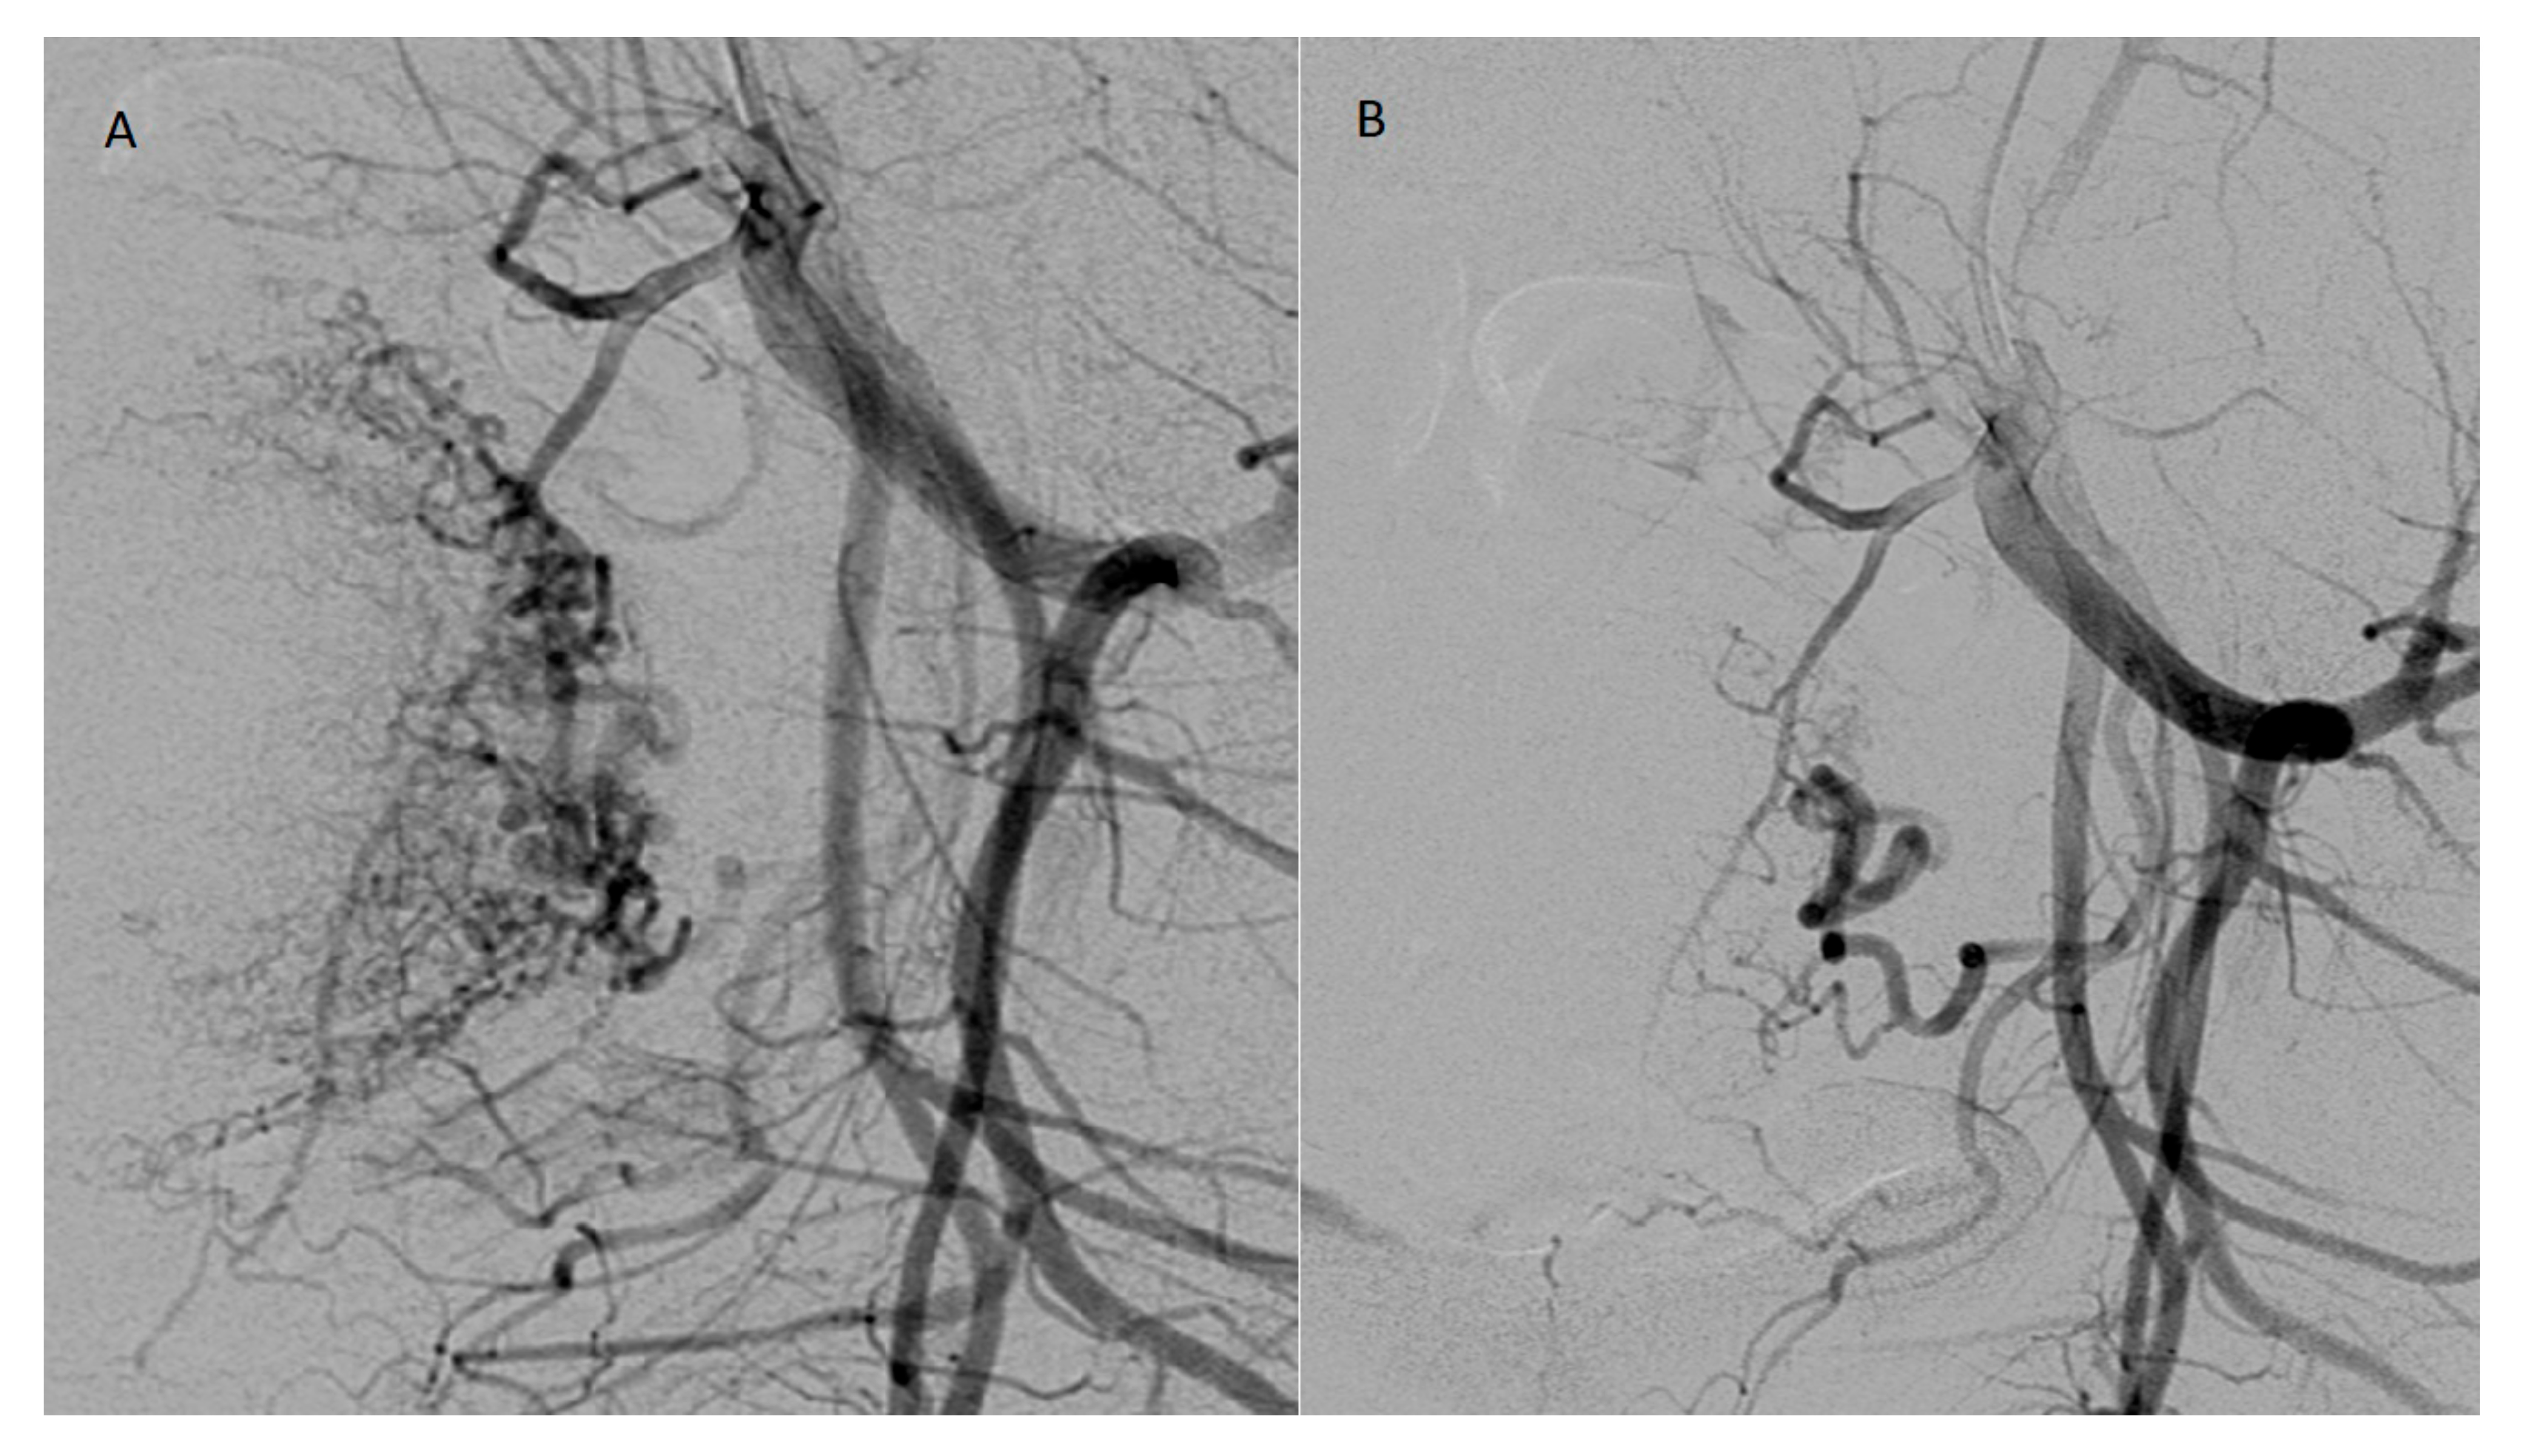

The diagnosis of RPOC was established based on clinical symptoms such as abnormal bleeding and transvaginal ultrasonography supplemented with color Doppler imaging. Sonographic criteria for RPOC included the presence of a heterogeneous intracavitary, predominantly hyperechoic focal mass, with or without increased vascularity [2]. Hypervascularity was classified based on color Doppler indices (color score 3 or 4). Transvaginal ultrasound in two RPOC cases are shown in Figure 1: one with minimal vascularity of the lesion and one case with highly vascular RPOC.

Figure 1. Transvaginal ultrasonography in 30-year old female with retained products of conception (RPOC) (A). Color Doppler ultrasound in the same patient showed minimal vascularity of the lesion (B). Transvaginal ultrasonography in 31-year old female with RPOC (C). Color Doppler ultrasound in the same patient showed hypervascularity of the lesion (D).